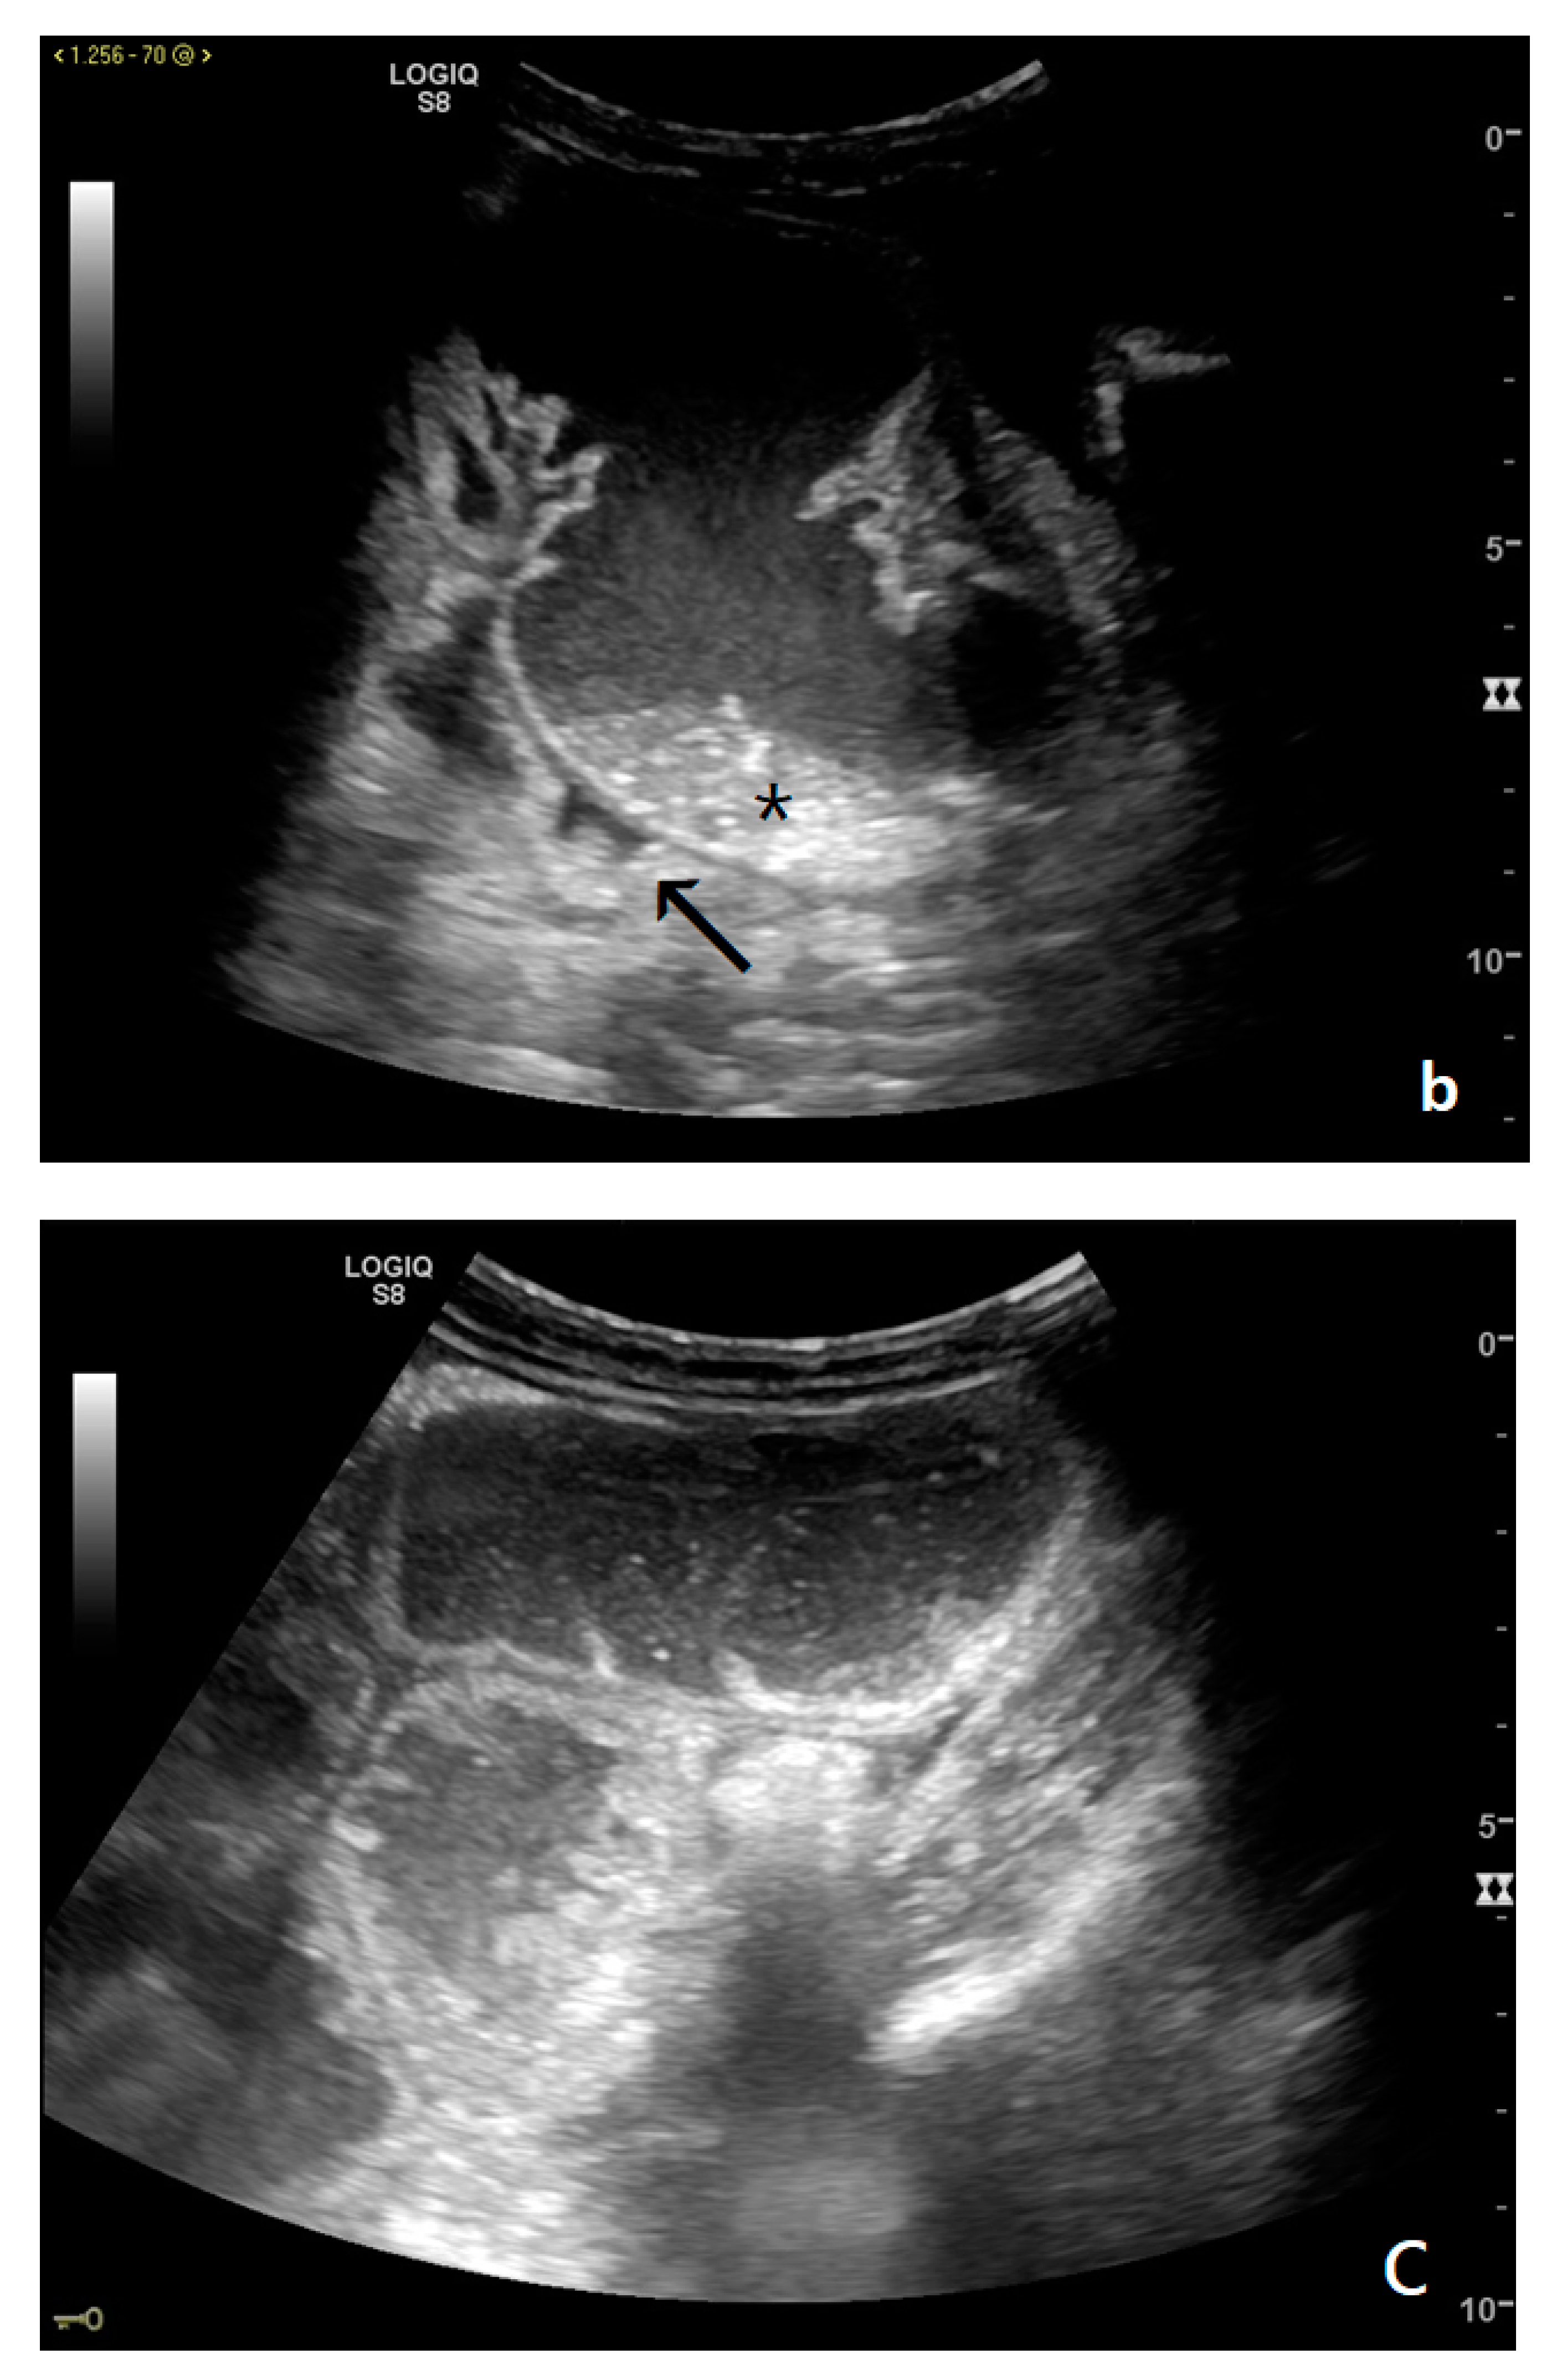

Figure 4.

A complicated SBO in a 69-year-old male with gastric cancer and peritoneal carcinosis. Ultrasound images show long (a) and axial (b) evaluations of a fluid-filled, dilated small bowel loop with hyperechogenic floating material (shown with an asterisk) (b,d). Bowel peristalsis was absent. Mild parietal and valvulae conniventes thickening are present (c,d). Downstream loops present normal caliber (bowel jump diameter). Free fluid is interposed between bowel loops (black arrow) (b).